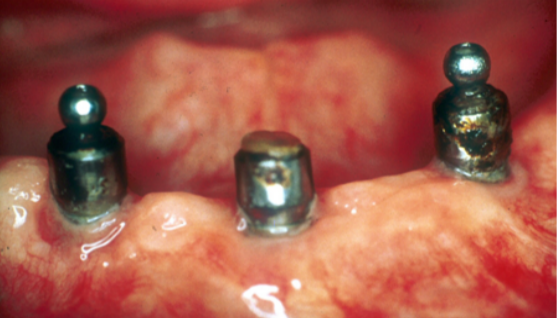

Non solo il framework e il corpo protesico vengono inficiati dall’attacco corrosivo ma anche abutment implantari come si può ben vedere dalle Fig. 20-a/b dove tre abutment per overdenture implanto ritenute inseriti su impianti posti nell’arcata mandibolare, presentano la superficie completamente corrosa che ha determinato anche la perdita della testa ritentiva di uno dei tre abutment.

Cr Co19 - Mesa Italia Cr Co20 - Mesa Italia Cr Co21 - Mesa Italia Cr Co22 - Mesa Italia